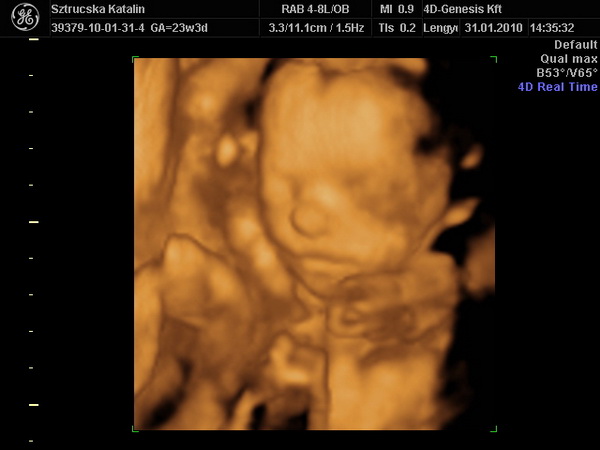

Tök jó, hogy ilyen szép nagyok a csajok! Holnap mindenképp megtippeltetem magunkat is Apánkkal. Már nekem is fúrja az oldalam a kíváncsiság. A mi fejünk sem volt túl nagy a múltkor...de már a 4D-n is úgy volt, hogy az oldalsó átmérő kisebb volt, elölről hátra nagyobb (tehát oldalról kicsit lapított a búránk) de így a körméret meg pont megfelelő lett. Pedig a képen milyen kis holdvilág képe van Nimókának.